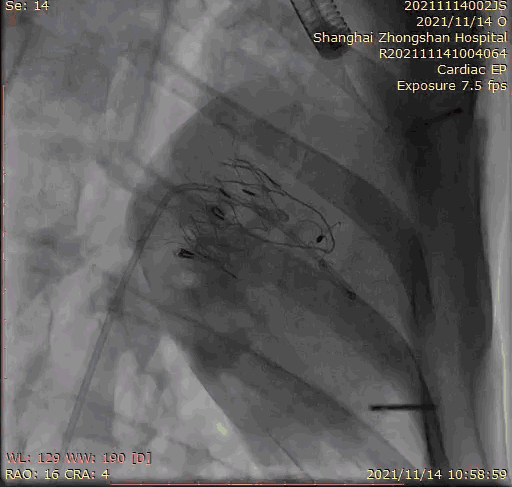

本次臨床前研究經(jīng)右側(cè)頸靜脈置入LuX-Valve Plus輸送系統(tǒng)可調(diào)彎鞘管,在DSA及超聲引導(dǎo)下將人工三尖瓣瓣膜植入到原有三尖瓣位置,利用獨特的錨定技術(shù)將人工瓣膜支架可靠固定在預(yù)定的位置。

上海中山醫(yī)院葛均波院士、錢菊英院長、周達新教授、潘文志教授、潘翠珍教授、李偉教授共同完成此次臨床前研究。術(shù)后葛均波院士對Lux-Valve Plus的器械操作性能給予了高度評價,DSA和超聲影像也顯示出在本次研究中Lux-Valve Plus的安全性和有效性俱佳。